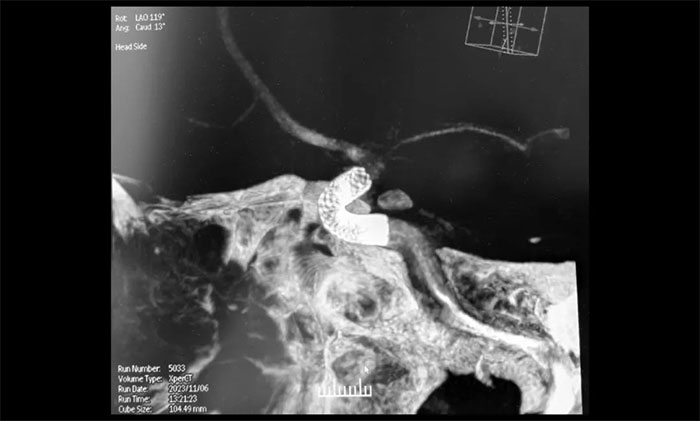

充分完善术前准备后,11月6日上午,席刚明教授在麻醉科和介入手术室紧密配合下,历时两个小时顺利进行了右颈内动脉眼动脉段多发动脉瘤血流导向装置(Pipeline)置入术。术中,微导管到位后缓慢释放血流导向装置到达术前预定位置,造影显示血流导向装置贴壁良好,完全封闭了动脉瘤瘤颈。多角度复查造影显示,动脉瘤瘤腔内有明显造影剂滞留,载瘤动脉和分支血管血流正常。术后CT检查,颅内未见出血,手术顺利完成,顺利拆除埋在患者脑子里的“不定时炸弹”。术后,患者顺利苏醒,无新发神经功能缺损。目前,患者已康复出院。

▲ 造影显示血流导向装置贴壁良好